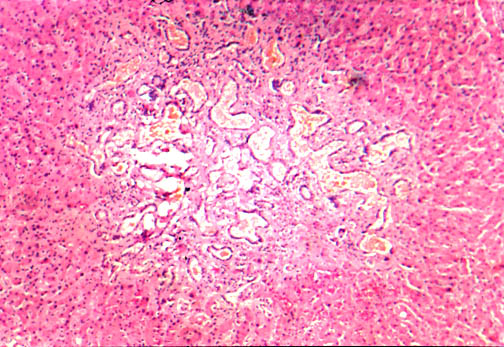

Fig. li-11-3-5. Congenital hepatic fibrosis. The parenchyma does not show any fibrous dissection nor regenerative nodules.

In this case you see dilated ducts and portal fibrosis. There is a combination of congenital ductal dilatation (Caroli' syndrome) and congenital hepatic fibrosis. |